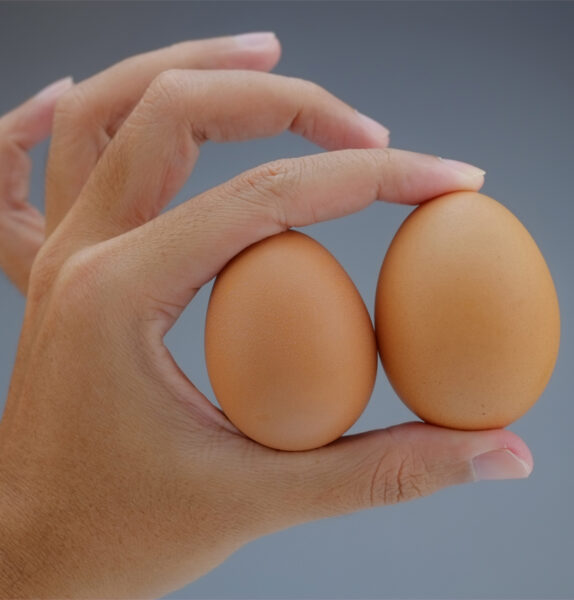

Η καλοήθης υπερτροφία του προστάτη είναι η αύξηση του μεγέθους του και σχετίζεται με την εκφύλιση των ιστών, όπως ακριβώς οι ρυτίδες και τα λευκά μαλλιά, αλλά δεν είναι πάθηση.

Η καλοήθης υπερτροφία του προστάτη είναι η αύξηση του μεγέθους του και σχετίζεται με την εκφύλιση των ιστών, όπως ακριβώς οι ρυτίδες και τα λευκά μαλλιά, αλλά δεν είναι πάθηση.